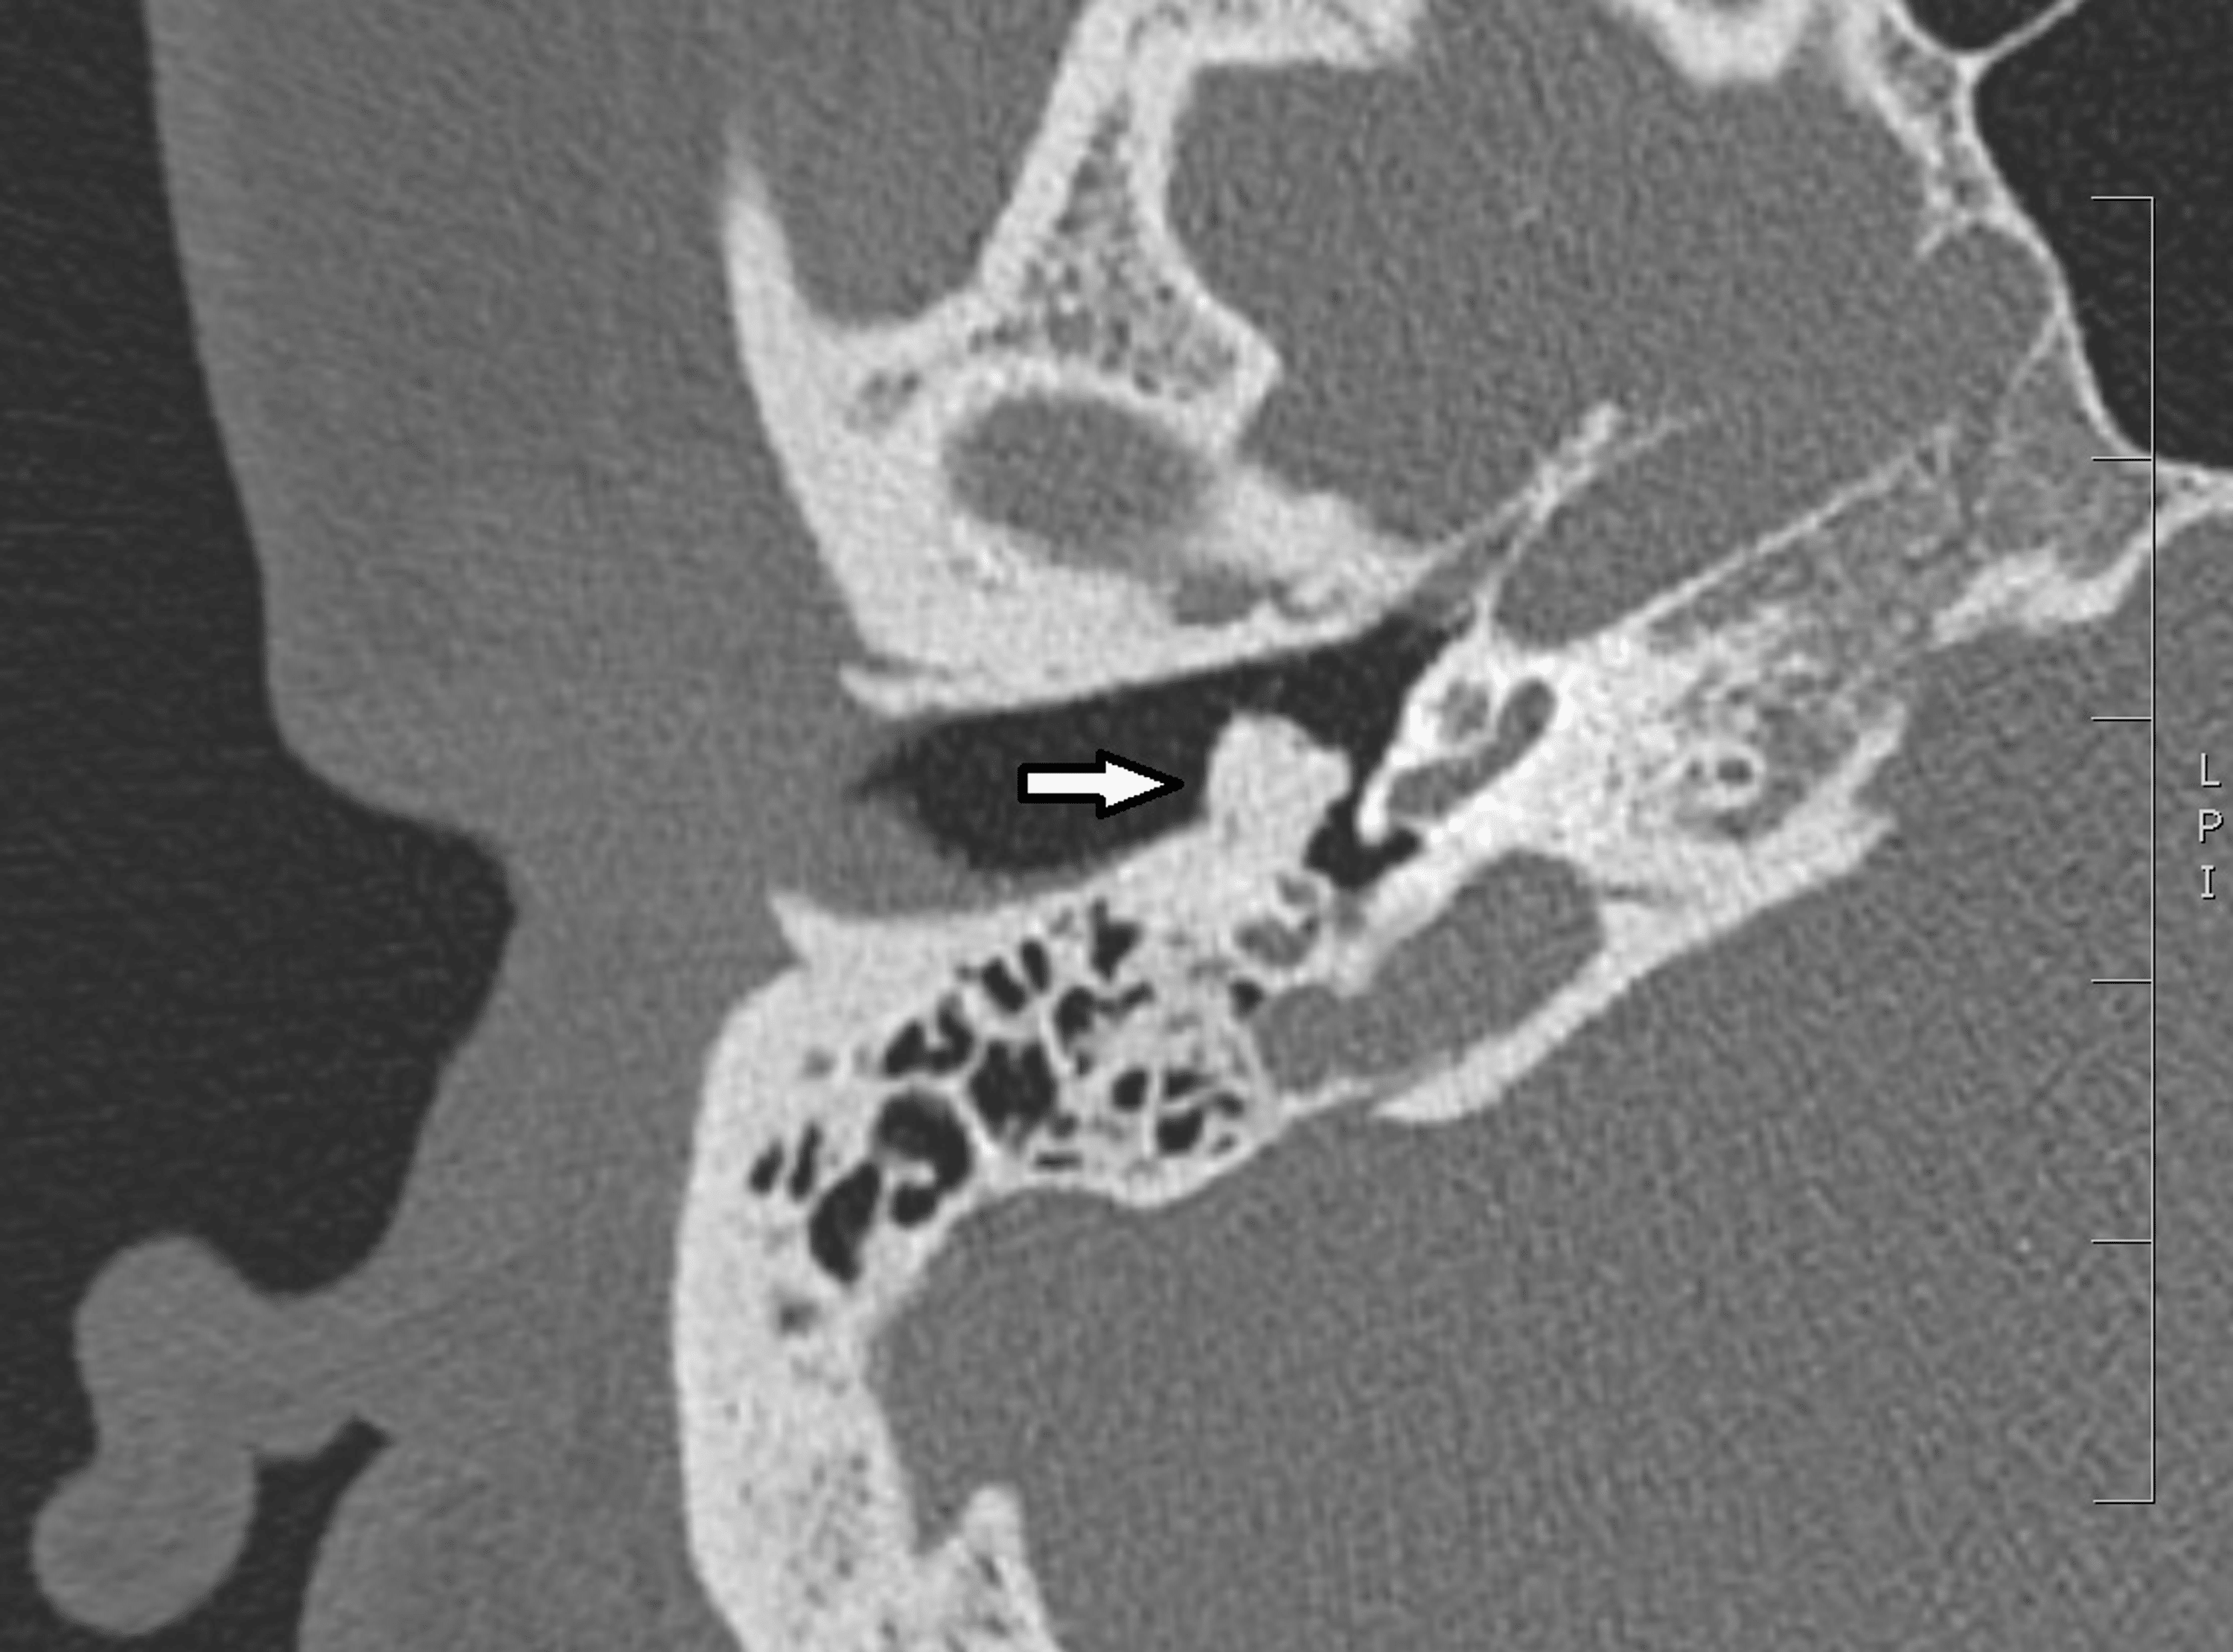

Ear Bone Dislocation. three tiny bones in your middle ear carry sounds to the inner ear. ossicular chain disruption (or ossicular discontinuity) is loss of normal alignment between the three middle ear ossicles. external stapediovestibular dislocation is a very rare condition of ossicular injury that can occur after. ossicular chain discontinuity (also called ossicular chain dislocation) is an abnormal separation of the middle ear bones. when conductive hearing loss persists more than 6 weeks after injury, ossicular chain dislocation must be. this is a review of the temporal bone ct scans of patients with a. If these bones are damaged or malformed, you may. This condition leads to conductive hearing loss as sound cannot be transmitted properly. Middle ear infections, injury or malformation of these bones can cause this condition. ossicular chain dislocation is a separation of the middle ear bones. It results in a hearing loss due to sound not being transmitted. The condition is a cause of conductive.

This condition leads to conductive hearing loss as sound cannot be transmitted properly. this is a review of the temporal bone ct scans of patients with a. If these bones are damaged or malformed, you may. ossicular chain discontinuity (also called ossicular chain dislocation) is an abnormal separation of the middle ear bones. The condition is a cause of conductive. ossicular chain disruption (or ossicular discontinuity) is loss of normal alignment between the three middle ear ossicles. external stapediovestibular dislocation is a very rare condition of ossicular injury that can occur after. It results in a hearing loss due to sound not being transmitted. Middle ear infections, injury or malformation of these bones can cause this condition. when conductive hearing loss persists more than 6 weeks after injury, ossicular chain dislocation must be.

Ear Bone Dislocation Middle ear infections, injury or malformation of these bones can cause this condition. external stapediovestibular dislocation is a very rare condition of ossicular injury that can occur after. Middle ear infections, injury or malformation of these bones can cause this condition. ossicular chain discontinuity (also called ossicular chain dislocation) is an abnormal separation of the middle ear bones. ossicular chain dislocation is a separation of the middle ear bones. this is a review of the temporal bone ct scans of patients with a. If these bones are damaged or malformed, you may. three tiny bones in your middle ear carry sounds to the inner ear. It results in a hearing loss due to sound not being transmitted. The condition is a cause of conductive. when conductive hearing loss persists more than 6 weeks after injury, ossicular chain dislocation must be. ossicular chain disruption (or ossicular discontinuity) is loss of normal alignment between the three middle ear ossicles. This condition leads to conductive hearing loss as sound cannot be transmitted properly.